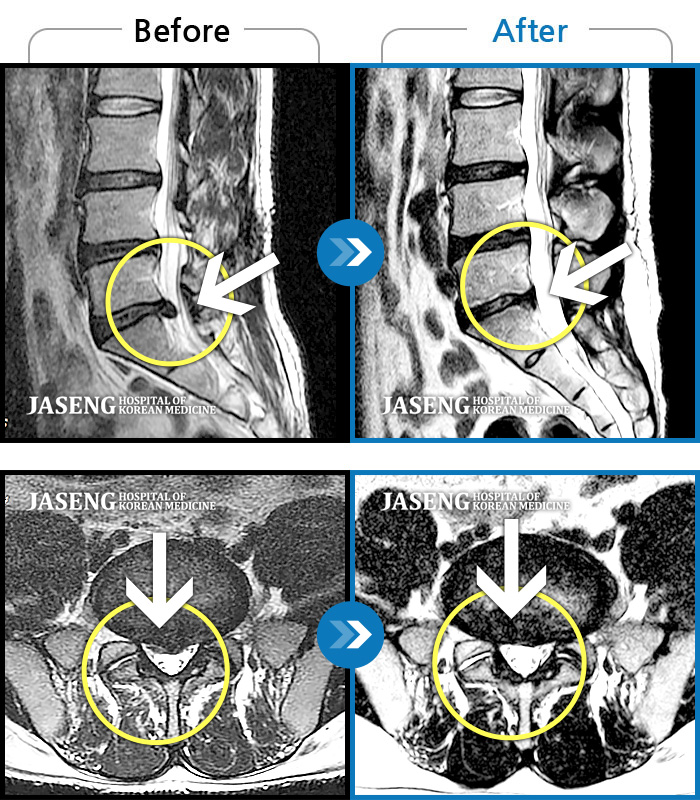

Before

After

허리 골반이 욱신욱신하게 아프고 우측 다리가 저렸다.

2018.03.09 ~ 2020.10.29